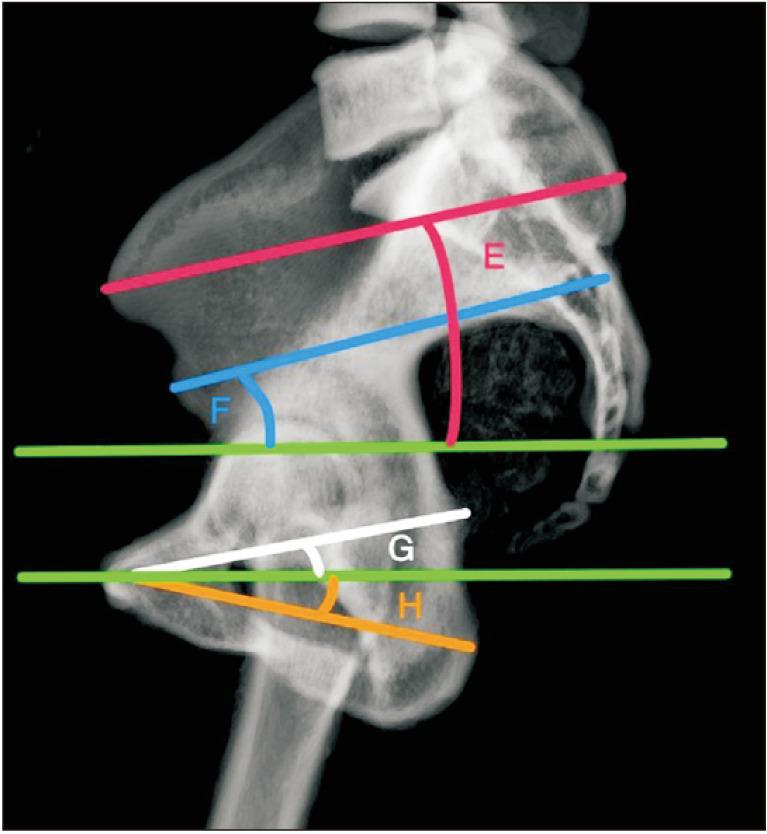

We defined four straight lines in pelvic 3D models: from the anterior superior iliac spine to the posterior superior iliac spine, from the anterior inferior iliac spine to the posterior inferior iliac spine, from the pubic tubercle to the ischial spine, and from the pubic tubercle to the ischial tuberosity. Similarly, we measured the angles formed by these lines using the vertical axis of the anterior pelvic plane on the horizontal plane and the horizontal axis on the sagittal plane. Additionally, we measured the distances between the femoral head centers and the acetabular centers in the coronal plane.

我们在骨盆 3D 模型中定义了四条直线:从髂前上棘到髂后上棘,从髂前下棘到髂后下棘,从耻骨结节到坐骨棘,从耻骨结节到坐骨结节。同样,我们在水平面测量了这些线与前骨盆平面垂直轴形成的角度,在矢状面测量了与水平轴形成的角度。此外,我们在冠状面测量了股骨头中心和髋臼中心之间的距离。